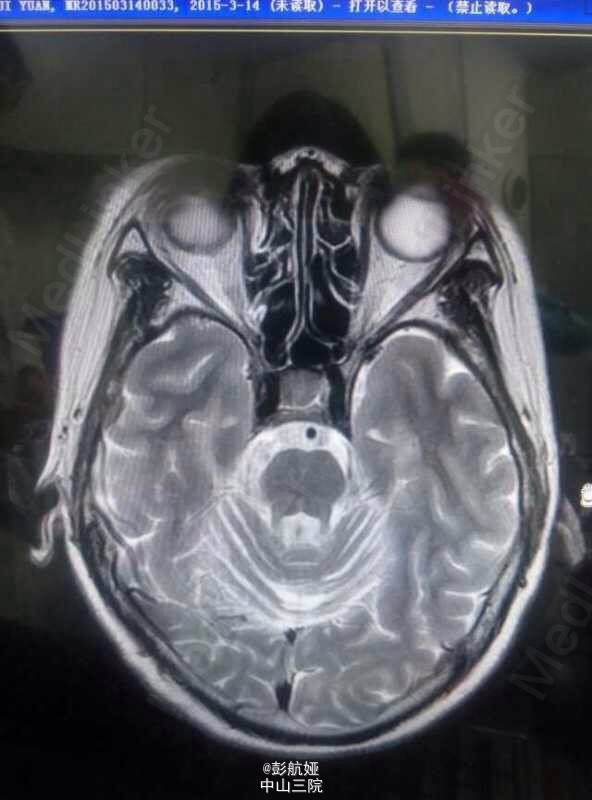

多系统萎缩-小脑型(MSA-C)

多系统萎缩

多系统萎缩MSA-C型1例

多系统萎缩C型一例

多系统萎缩?